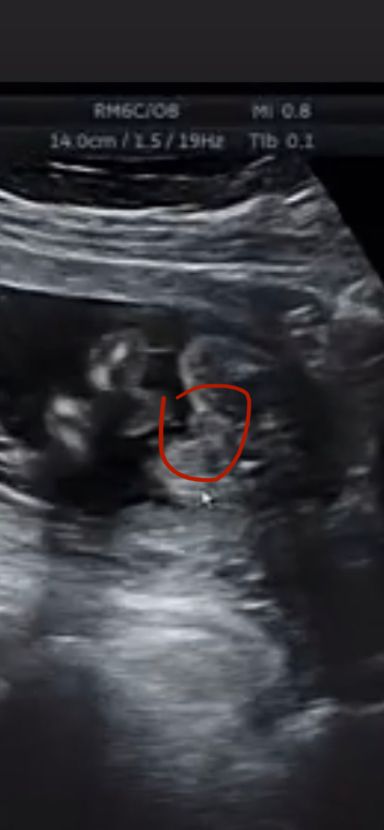

На узи сказали мальчик, могли ли ошибиться?

Сбрасывала сюда уже фото, большинство писали, что девочка скорее всего, показывали фото узи своих мальчиков и у нас прям не так.

Поэтому закрались сомнения в достоверности, хотя узи делала на сроке 17 недель.. может ли быть ошибка? Или тут мальчик всё-таки явный?))

У девочек еще на двое разделено.

Но на плохом аппарате узи можно принять пуповину между ног за мальчика (у нас так было), у вас, и правда, не классическая картинка "мальчика":) Если ещё пойдёте на узи, просите с доплером посмотреть, с ним пуповина или нет видно будет)))

Ошибки конечно могут быть, но мне видится мальчик, у меня так же на узи, тоже в 17 недель сказали мальчик

Мальчик, на фото мошонка, у нас так же было, у девочек совсем не так